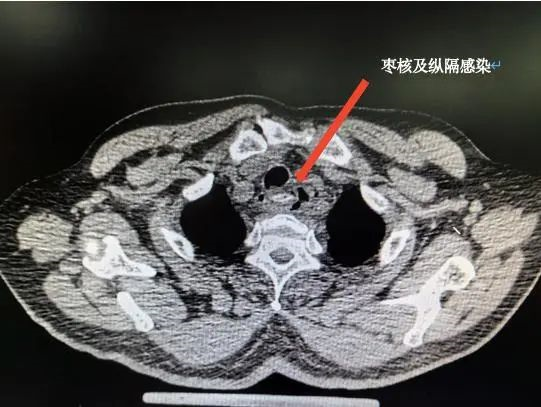

不久前的一天,74岁的程先生因为胸部疼痛不适、高烧且吞咽困难来到北京天坛医院急诊就诊。“胸部CT显示,老人食管上段有条状稍高密度影,伴周围多发气体。”接诊的胸外科副主任医师真德智说,老人告诉他,大约5天前吃东西时,误吞了一个枣核,当时吃了点其他食物想着“压一压”就好了,没想到症状不但没缓解,还发起烧来,吃退烧药都不管用。“综合老人自述的情况,判断很可能是枣核导致的穿孔和纵膈感染。”随后,老人被紧急收住院,胸外、消化等专业的专家会诊后迅速进行手术治疗。

就在程先生的手术结束后没多久,又有一位被枣核所累的患者来到北京天坛医院急诊。今年75岁的魏女士经历与程先生几乎一模一样,同样是误食枣核后自行吞咽食物,随后出现吞咽困难、疼痛不适等症状,胸部CT显示食管异物。急诊手术发现,枣核横在食管上段,导致食管穿孔。住院治疗15天后,魏女士痊愈出院。